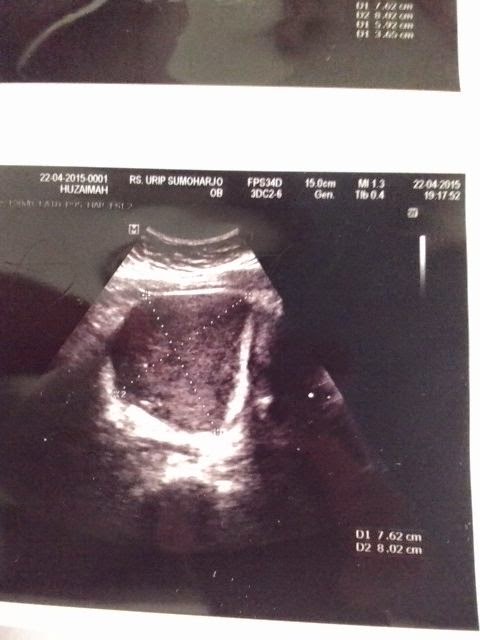

Sore itu sekitar jam 16:53 tanggal 20 Mei 2015 saya berbincang dengan mbak Hu (sebut saja begitu untuk privasi), berbincang-bincang via BBM dan beliau menceritakan kalau ukuran kista saat sebelum minum ladyfem berukuran sekitar 7,62 cm dan 8,02 cm pada tanggal 22 April 2015. Berikut dibawah ini penampakan gambar hasil usg sebelum rutin minum Ladyfem.

Foto Hasil USG Sebelum Minum Ladyfem |